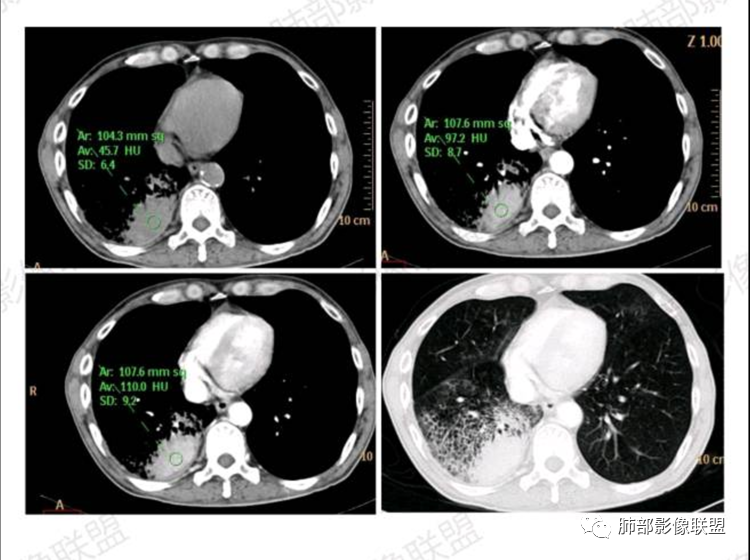

2.影像显示右肺较广泛蜂窝样阴影,上肺及下肺为主,未见液平及重力分布趋势。其中上叶后段及下叶后基底段近胸膜下可见实性密度区,实性密度区强化明显,周边特征掩盖不清。

2.单肺或单肺叶蜂窝样阴影,CYFRA211增高等应当高度警惕恶性肿瘤,尤其是出现异常强化的实性密度区。正如有老师分析肺腺癌可能性较大!

3.尽管患者咳大量白色泡沫痰,但病灶区未显示重力分布趋势,大范围病灶并未见播散结节,粘液腺癌的可能性降低。病灶浸润破坏能力不强(蜂窝样结构尚存,胸膜受侵较迟等),强化较显著等,肺鳞癌可能性较小。